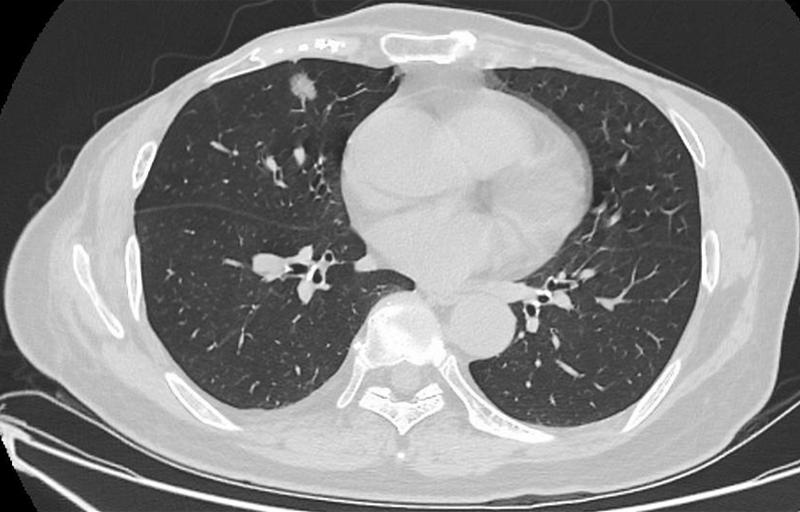

肺結(jié)節(jié)是指肺部出現(xiàn)的直徑小于3厘米的圓形或類圓形病灶,大多數(shù)肺結(jié)節(jié)是良性的,但部分可能需要治療,肺結(jié)節(jié)的癥狀因個(gè)體差異而異,部分患者在早期可能無任何癥狀,因此定期進(jìn)行體檢至關(guān)重要。